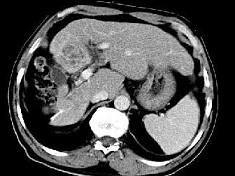

问题 女性,56岁,腹胀、双下肢浮肿、乏力、食欲不振,影像所见如下图,最佳的诊断是 ( )

选项 A.酒精性肝硬化并肝血管瘤 B.血吸虫肝硬化并肝癌 C.肝炎后肝硬化并肝癌 D.局限性脂肪肝 E.原发性肝癌

答案 B